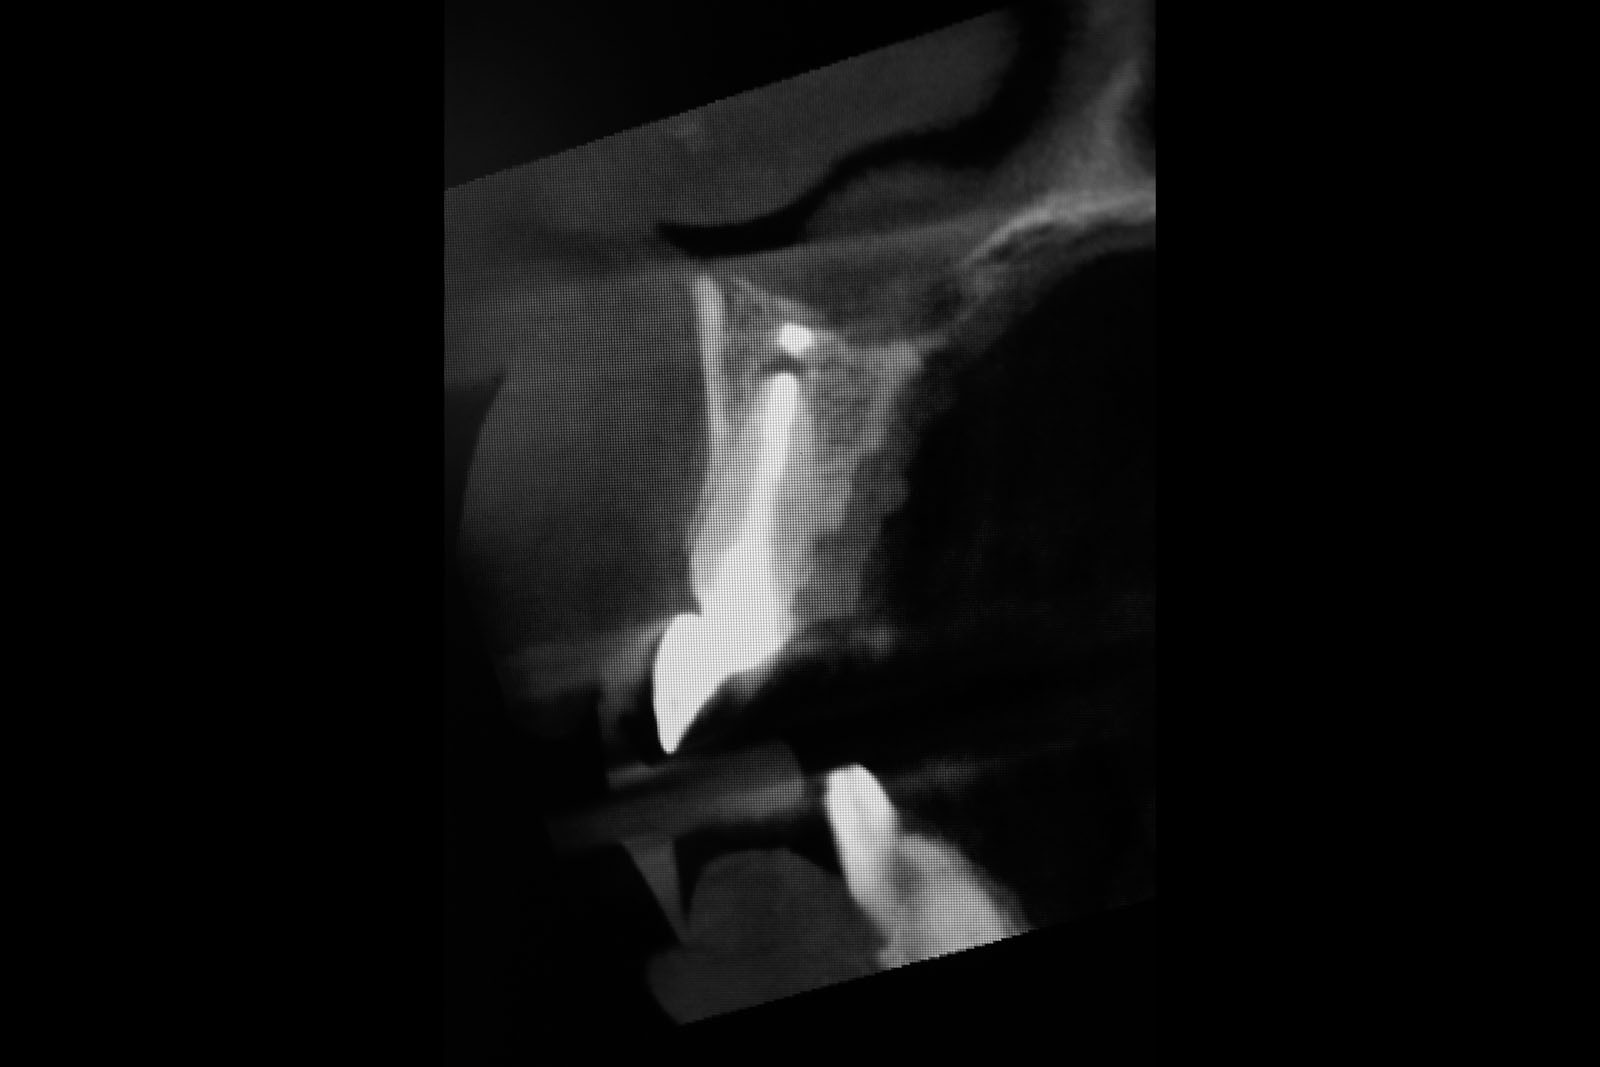

Zabiegiem, który rozwiązuje ten problem, jest podniesienie dna zatoki szczękowej, czyli odbudowa kostna w okolicy zębów trzonowych. Ubytek kości uzupełniany jest materiałem kościotwórczym, który układany jest pod błoną wyścielającą zatokę szczękową, zwaną membraną Schneidera. Zmniejszając objętość zatoki szczękowej, tworzy się tym samym stabilną strukturę kostną, umożliwiającą zabieg implantacji wszczepów śródkostnych.

ANATOMIA ZATOK SZCZĘKOWYCH:

Zatoki szczękowe to symetrycznie umieszczone w kościach szczęk przestrzenie powietrzne, posiadające komunikację z jamą nosa. Średnio pojemność zatok wynosi 24 cm3, a ściany wyścielone są błoną śluzową (membrana Schneidera). Dno zatoki szczękowej stanowi wyrostek zębodołowy, w którym umieszczone są zęby, często zlokalizowane tuż pod cienką wyściółką zatoki. Statystycznie najwęższy obszar kostny w tej strefie zlokalizowany jest na wysokości zębodołów pierwszego i drugiego zęba trzonowego.

METODY OPERACYJNEGO PODNIESIENIA DNA ZATOKI SZCZĘKOWEJ:

• Metoda otwarta – opisana w 1980 przez Jamesa i Boyna – polega na chirurgicznym dostępie do zatoki szczękowej poprzez jej boczną ścianę, następnie delikatnej preparacji, oddzieleniu wyściółki (błony Schneidera) bez jej perforacji, umieszczeniu pomiędzy nią a dnem zatoki materiału odbudowującego kość. Zabieg podniesienia dna zatoki szczękowej może przebiegać z jednoczesnym wszczepieniem implantów lub wszczepieniem ich w czasie odroczonym o 6–8 miesięcy. Warunkiem jednoczesnego wszczepienia implantów jest możliwość pierwotnie stabilnego ich umocowania w pozostałej własnej kości wyrostka zębodołowego. Najmniejsza jej ilość wg niektórych autorów to 1 mm.

• Metoda zamknięta – opisana w 1994 przez Summersa – bez szerokiego otwierania zatoki szczękowej, stosowana w sytuacjach wymagających niewielkiego zakresu rekonstrukcji na wysokość. W tej metodzie materiał regeneracyjny do odbudowy kości wprowadza się przez nawiercony kanał, komunikujący się z zatoką w pozycji zaplanowanej do wszczepienia implantu, lub tylko kondensuje się (zagęszcza, rozpycha i wydłuża) obszar kości dla uzyskania stosownej jej ilości i gęstości dla stabilnego umocowania implantu. Zabieg odbudowy kostnej wg Summersa wykonuje się przy użyciu specjalnego instrumentarium – zestawu osteotomów. Uzyskuje się dodatkowo 2–4 mm kości na wysokość